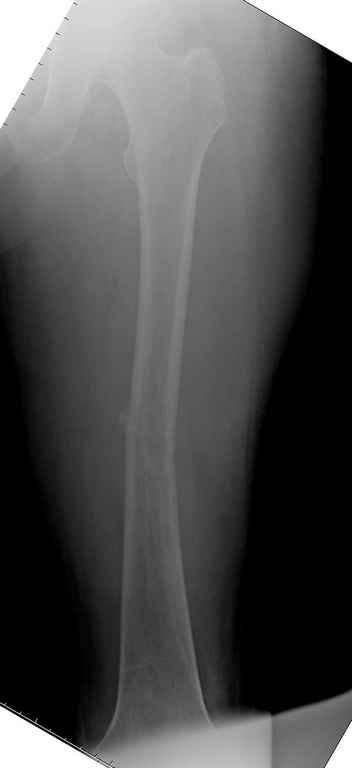

Здесь случай 66 летней пациентки со спонтанными болями в левой нижней

конечности, обратилась в приемное, сделаны снимки бедра и КТ.

Патологический перелом бедра, конечность на вытяжении.

Имя     : Pathologic Femur CT 2.jpg